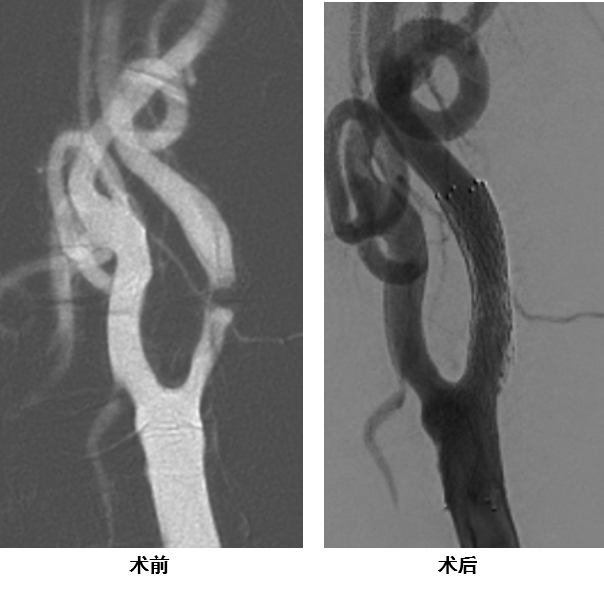

病例一

病变位置高,且主动脉弓部条件极差(多发溃疡+附壁血栓),TF-CAS风险极高,CEA亦非最佳选择。